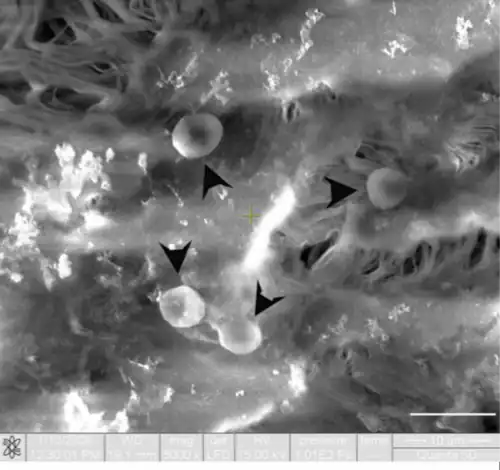

![]() Células endoteliales (en el centro) abrazando un eritrocito (E). Un pericito a la izquierda. | ||